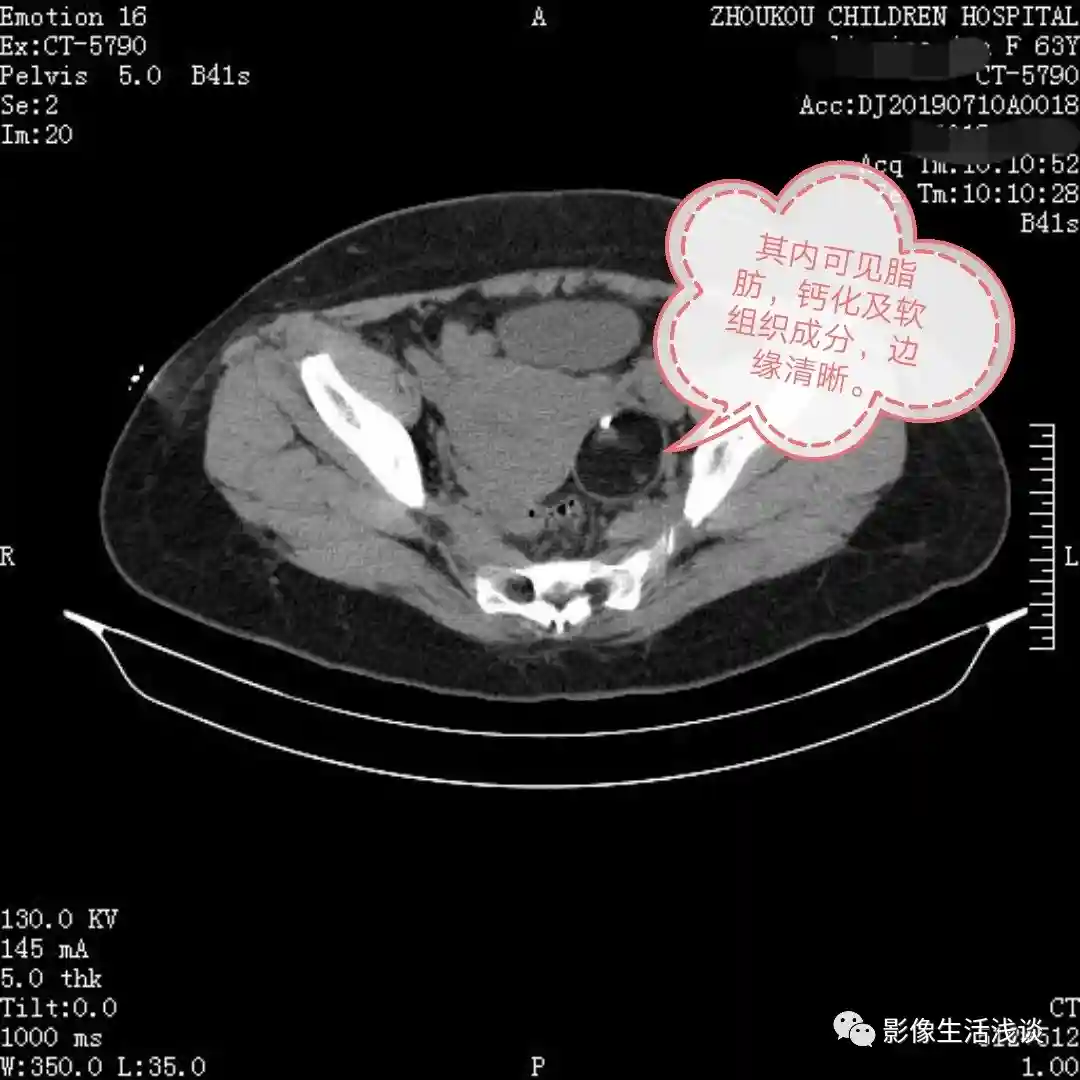

今天给大家分享的第一病例7岁女孩,以右下腹痛来诊,在CT平扫检查中我们发现:右侧附件区可见囊性占位,以液性为主,其内可见脂肪成分及点状钙化影,边界清晰。考虑:右附件区畸胎瘤